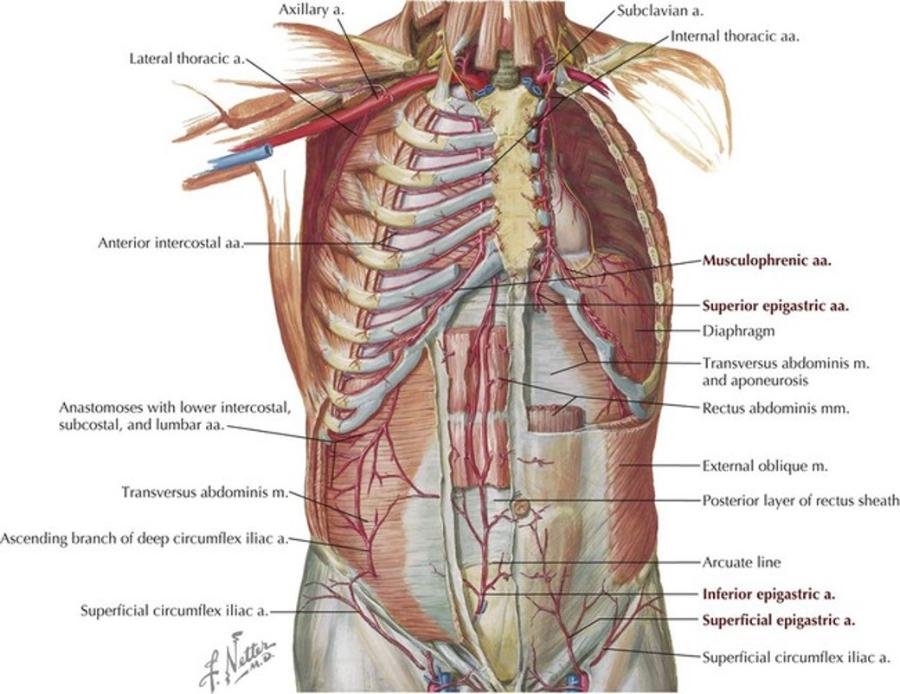

- Blood supply to the rib cage originates from what 2 places?

- what 2 arteries supply the intercostal spaces of the rib cage

- what branch off of the subclavian artery goes down specifically to the diaphragm?

aorta and subclavian artery

Anterior and posterior intercostal arteries

notice how branches from the aorta go around and supply the rib cage

the internal thoracic artery

look at picture

study picture

Anterior intercostal arteries:

- These arteries branch from where?

- then this originates from where?

internal thoracic artery

- Internal thoracic artery originates from subclavian artery

the internal thoracic artery comes from the ____________ vein and then runs behind the anterior ________?

subclavian vein

anterior sternum

notice the internal thoracic artery coming down right near the sternum

The Anterior intercostal arteries supply which intercostal spaces?

- The lower intercostal spaces supplied by what?

1-9

posterior intercostal arteries

notice how the intercostal arteries run superior and inferior in the intercostal spaces

look at all the arteries and their relationship

look at how the posterior intercostal arteries come from the back and wrap around the intercostal spaces from the back

look at picture

what artery may be used as a bypass graft?

the left internal thoracic artery